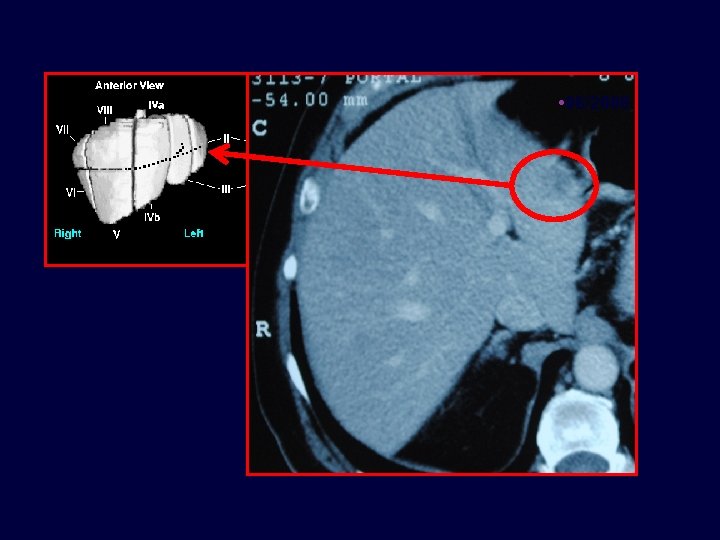

• Caso clínico • Paciente de 71 años con cáncer de colon estadío III en 07/2004, Metástasis hepáticas en 06/2008 • 65 años, enfermedad coronariana, médico. Resección carcinoma de colon T 3 N 1 M 0 • 07/2004 • Termina FOLFOX x 12 03/2005 06/2008 11/2008 06/2010 • - Lesiones hepáticas – ambos lóbulos

• 06/2008